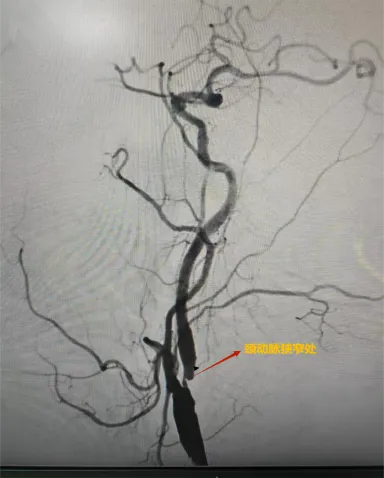

邵阳日报·邵阳新闻在线讯(通讯员 林海英)10月10日,神经内科一区收到了一封感谢信,来自一位因颈动脉狭窄进行了支架置入术的患者。患者从入院检查到完成手术康复出院仅用时三天,邵阳市中心医院神经内科介入团队让患者体验到了“微创手术+快速康复”的惊喜。

颅内动脉狭窄是导致缺血性脑卒中的重要原因,而支架植入术是有效的预防手段。该手术操作极其精细,容错率低。近年来,随着国家对于卒中防治体系建设的投入,该院神经内科介入团队手术量持续增长,技术的熟练度带来了手术成功率的显著提升和并发症发生率的明显下降。